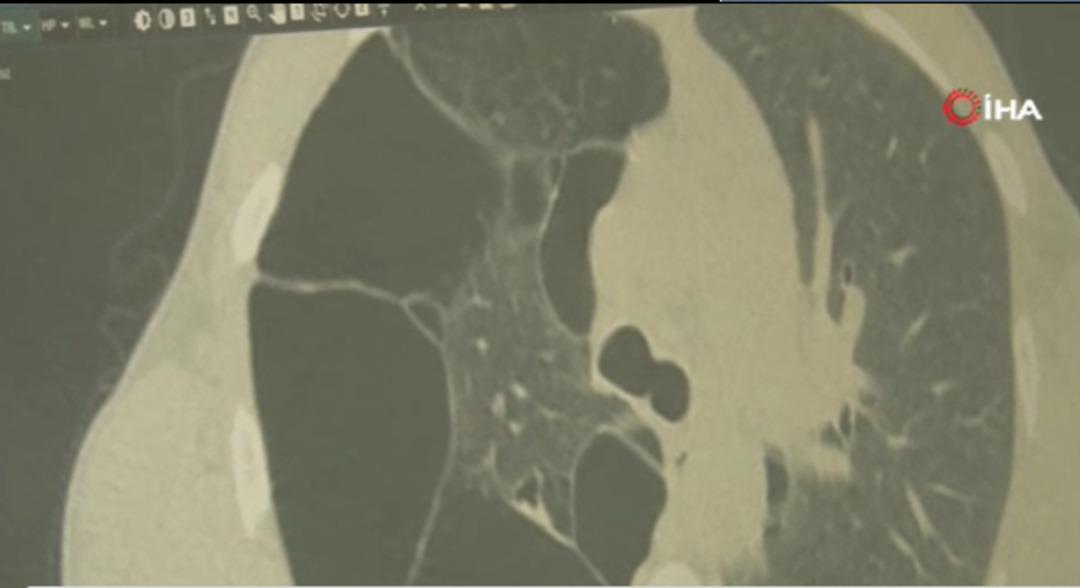

Tetkiklerde kalsiyum değeri yüksek bulunurken taramalarında paratiroidde nodül, böbreküstü bezinde kalınlaşma, sağ akciğerinde yaygın büyük hava kistleri dışında sağ akciğer alt lobunu uzun süredir kapalı tutan bir tümör tespit edilerek MEN2 hastalığı bulunduğu belirlendi.

Tedavi sürecine yönelik bilgi veren Prof. Dr. Atinkaya Baytemir, "Endokrin ve diğer bölümlerle yaklaşık 3,5 aylık multidisipliner bir sürecimiz oldu. Çok titiz, özenli, aşama aşama hastada tedavi ve tetkik sürecini geçirdik. Hastadaki asıl problem; MEN dediğimiz genetik geçişli, ailesel bir sendrom olması. Hastamızın akciğerinde sadece alt parçadaki tümör değil bir de üst parçada çok büyük dev hava kisti dediğimiz kistleri mevcuttu. 30 yaşında bir erkek hasta, sağ akciğerin nerdeyse 4-5'te bir alana sahipti. Sağ akciğerdeki bu lezyonun olduğu hava yolunda sadece tümörlü alanı çıkardık, çıkardıktan sonra akciğerin cevabı da çok güzel oldu, açıldı. Hasta önemli bir akciğer kaybına uğramadı. Sigara kullanıyor, bırakmasını tavsiye ettik. Dünyada 35 binde bir görülen bir hastalık MEN2 Sendromu diye geçiyor, çok nadir bir hastalık. Multidisipliner yaklaşılması çok önemli. Son derece ender bir sendrom. Ömür boyu takip edilecek, kötü huylu bir tümör çıkmadı. Çıkan bütün lezyonlar iyi huylu. Hastamızın sağlıklı bir yaşam sürdürmesini bekliyoruz. 15 ila 30 yaş arasında genellikle semptomlar görülmeye başlıyor. Hasta önemsemezse tansiyon şikayeti, kan tükürme, sigara içmeye devam eder ama bununla ilgili bir kontrole gelmezse atlanabilir" dedi.